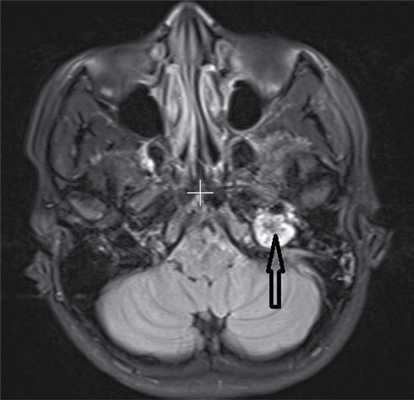

По данным МРТ с контрастным усилением в проекции верхушки пирамиды височной кости с распространением на область луковицы левой яремной вены определялась негомогенная структура неправильно-округлой формы, размером около 15×17×21 мм, интимно прилежащая к левой внутренней сонной артерии, а также к твердой мозговой оболочке задней черепной ямки. Опухоль активно накапливала контрастное вещество (рис. 2). Рис. 2. МРТ основания черепа. В области верхушки пирамиды височной кости слева — гломусная опухоль (указана стрелкой), прилежащая к внутренней сонной артерии.